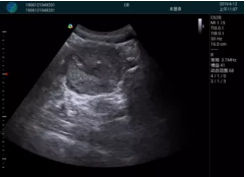

清晰顯示腺體內(nèi)低回聲快影,邊界清晰,包膜較光滑

腺體內(nèi)部清晰顯示一低回聲塊影,形態(tài)不規(guī)則,邊界模糊,邊緣呈毛刺狀,內(nèi)部見(jiàn)砂礫樣鈣化